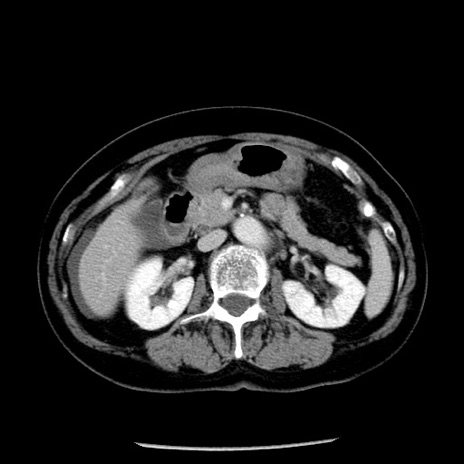

冠状断像

【症例】70歳代女性

【主訴】腹痛、嘔吐

【現病歴】15時間程前(昨晩)より腹痛あり。今朝になっても症状の改善なく、嘔吐あり。腹痛も増悪あり、救急外来受診。

【既往歴】子宮癌全摘術後

【身体所見】意識清明、BP 121/72mmHg、P 74bpm、SpO2 100%(RA)、腹部:平坦・軟、腸雑音ほぼ聴取せず。下腹部・心窩部・臍左上に圧痛あり。反跳痛なし。

【データ】WBC 10600、CRP 0.15